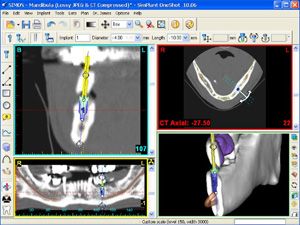

安全性の追求という意味において、当院では、埋め込み手術に先立って、CT(コンピュータトモグラフィー)撮影を行い、そこから得られた詳細な情報(埋め込む部位の骨の高さ、幅、骨密度など)から、インプラント治療経験が豊富な複数の歯科医師がカンファレンスで検討し、治療計画を立案しています。これにより、成功率は飛躍的にアップしていると考えています。